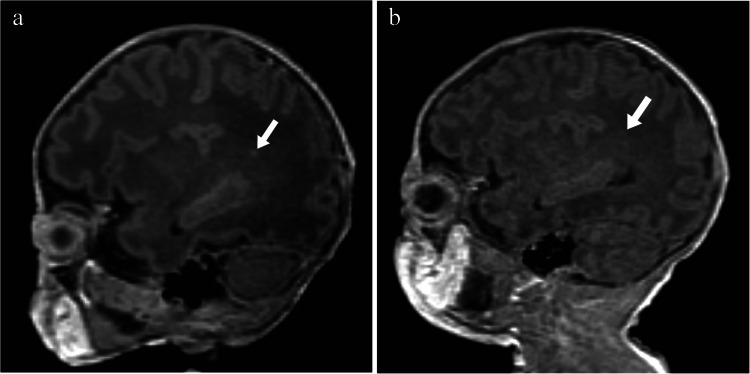

Abstract Image